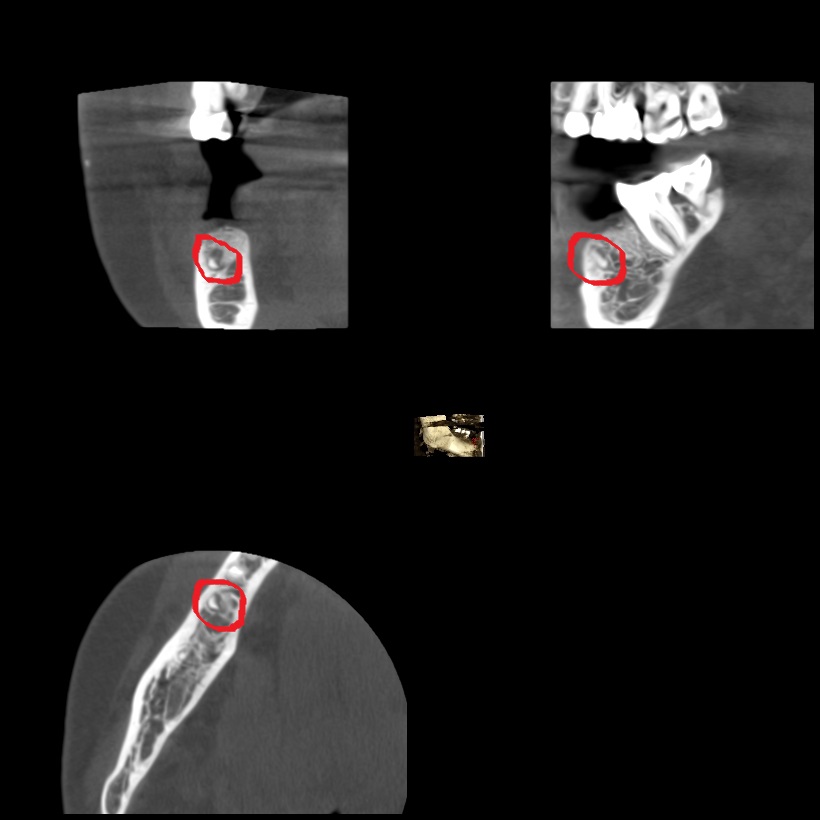

From www.temeculafacialoralsurgery.com

XRay of Tooth Fragment from Previous Extraction 1 Tooth Removal Bone Fragment In the mouth, bone spicules may occur following tooth extraction or other kinds of oral surgery. Read this blog to know if sharp bone fragments in the gum need immediate removal. Your best bet is to follow up with your dental professional for their expert insight and recommendation. A bone spicule is a fragment of bone that become exposed after. Tooth Removal Bone Fragment.

XRay of Tooth Fragment from Previous Extraction 2 Tooth Removal Bone Fragment These bone fragments, also known as dental bone spurs, can form when a tooth is removed. Some dentists may refer to these as bone sequestra. Your best bet is to follow up with your dental professional for their expert insight and recommendation. Conservative management, manual removal or surgical removal. Understanding bone spicules following tooth extraction is crucial for anyone undergoing. Tooth Removal Bone Fragment.